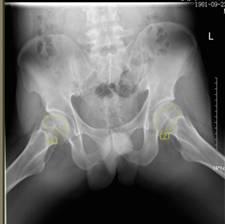

術(shù)前報告顯示患者雙側(cè)股骨頭壞死

37歲的患者吳先生反復(fù)雙髖疼痛2月余,聽說瀘州市中醫(yī)院在治療骨科疾病方面很有經(jīng)驗,遂來到醫(yī)院治療。經(jīng)檢查,吳先生雙側(cè)股骨頭壞死(II期),如不及時進行手術(shù)治療,他的股骨頭將進一步壞死至骨頭塌陷,引發(fā)關(guān)節(jié)炎,嚴(yán)重時,必須行關(guān)節(jié)置換術(shù)。這樣,將會給吳先生的生活質(zhì)量及經(jīng)濟帶來嚴(yán)重負(fù)擔(dān)。

考慮患者發(fā)病程度為早期,疼痛時間不長且比較年輕,瀘州市中醫(yī)院骨傷三科主任、主任中醫(yī)師李彬決定為他實施雙側(cè)股骨頭壞死髓芯減壓+PRP術(shù)進行保髖治療。